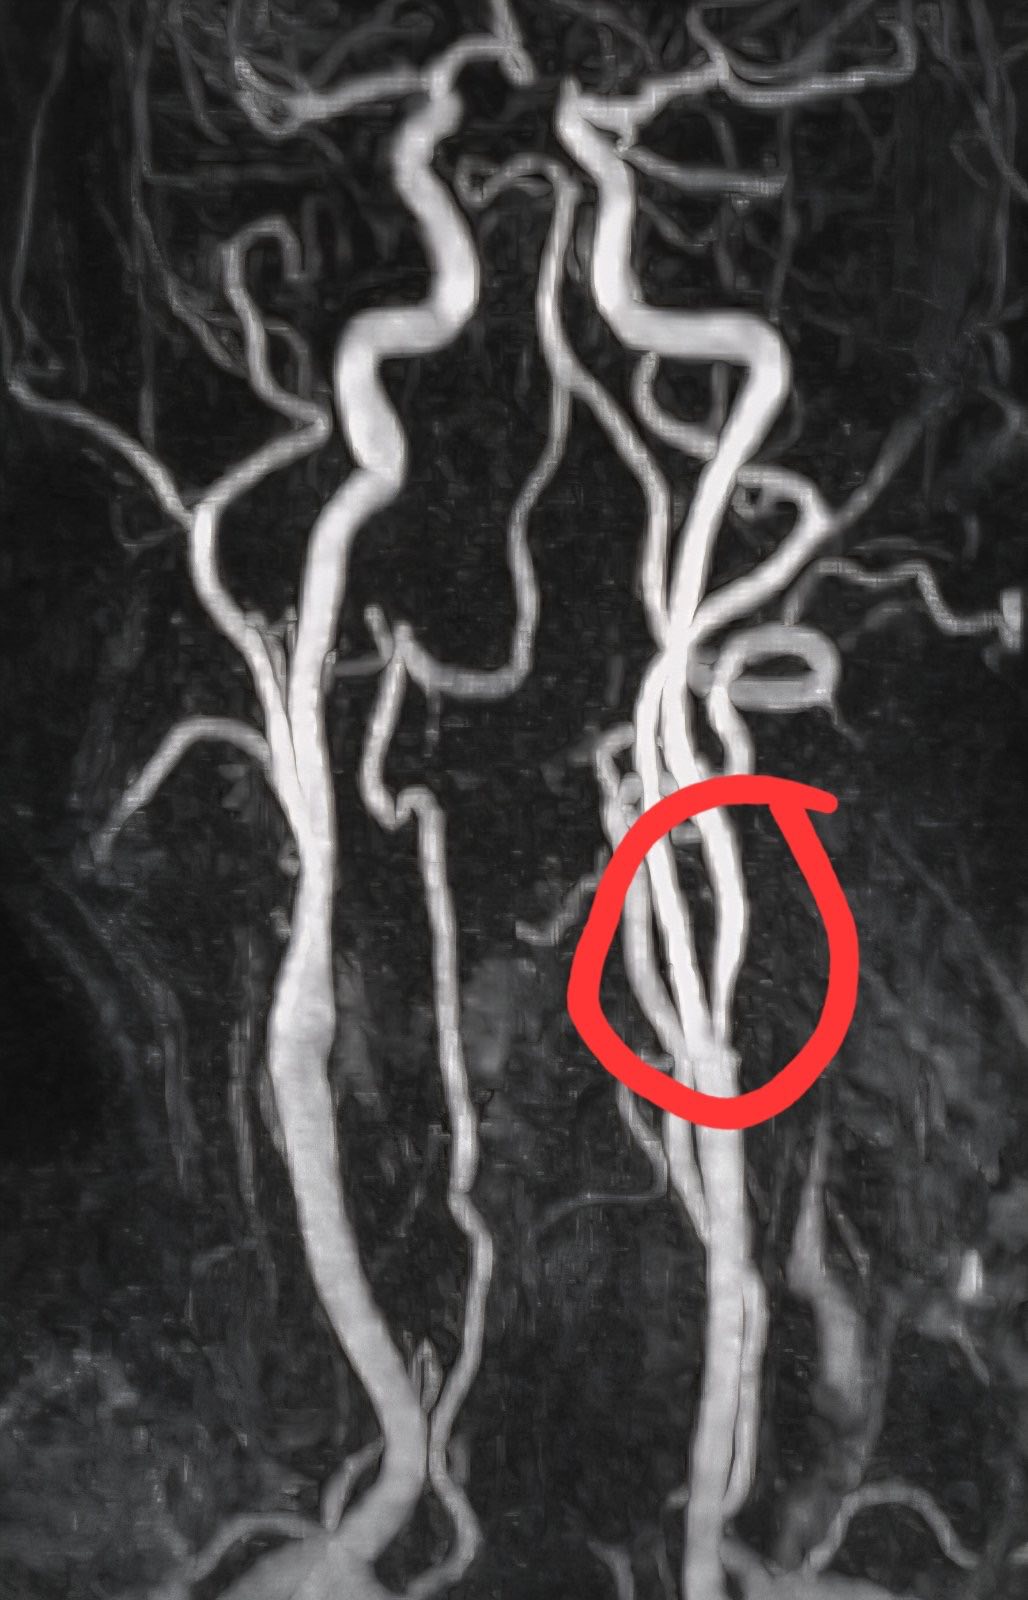

Την επιτυχή ενδαρτηρεκτομή της αριστερής έσω καρωτίδας σε ασθενή 67 ετών, ο οποίος πρόσφατα υπέστη ισχαιμικό εγκεφαλικό επεισόδιο.

Για πρώτη φορά σε περιφερειακό νοσοκομείο της Δυτικής Μακεδονίας πραγματοποιείται μια τόσο απαιτητική και υψηλής εξειδίκευσης χειρουργική επέμβαση, γεγονός που αποτελεί ορόσημο για την περιοχή μας και τις δυνατότητες του δημόσιου συστήματος υγείας.